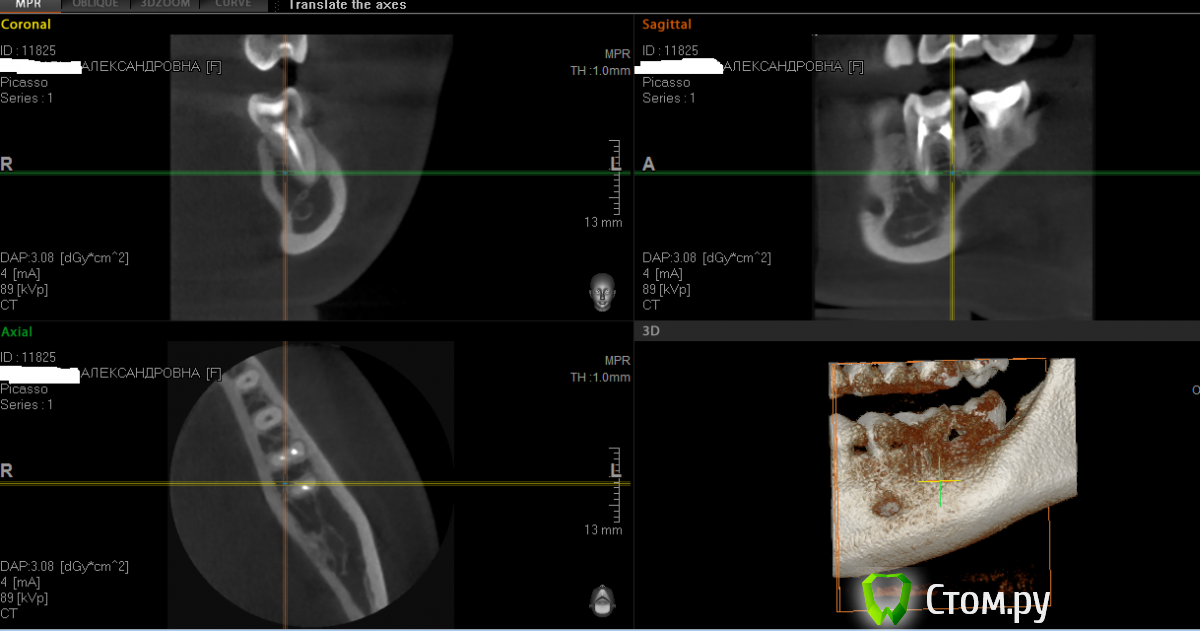

july88 Опубликовано 19 ноября, 2014 Автор Поделиться Опубликовано 19 ноября, 2014 Покажите новый снимок сделала КТ в пикассокак выложить непонятно Ссылка на комментарий

july88 Опубликовано 20 ноября, 2014 Автор Поделиться Опубликовано 20 ноября, 2014 http://my-files.ru/04spwx.кт.zip Ссылка на комментарий

july88 Опубликовано 21 ноября, 2014 Автор Поделиться Опубликовано 21 ноября, 2014 (изменено) мой лечащий доктор никаких отклонений по снимкам КТ не увидел...уже не знаю что делать, боль стала отдавать и в верхние 6,5, хотя они живые и были летом пролечены от кариеса, в ухо, хочется подвигать челюстным суставом. Могла ли остаться инфекция в 7 зубе после лечения?есть ли смысл пропить цифран ст 5 дней?планирую беременность и оч переживаю по этому поводу.... Изменено 21 ноября, 2014 пользователем july88 Ссылка на комментарий